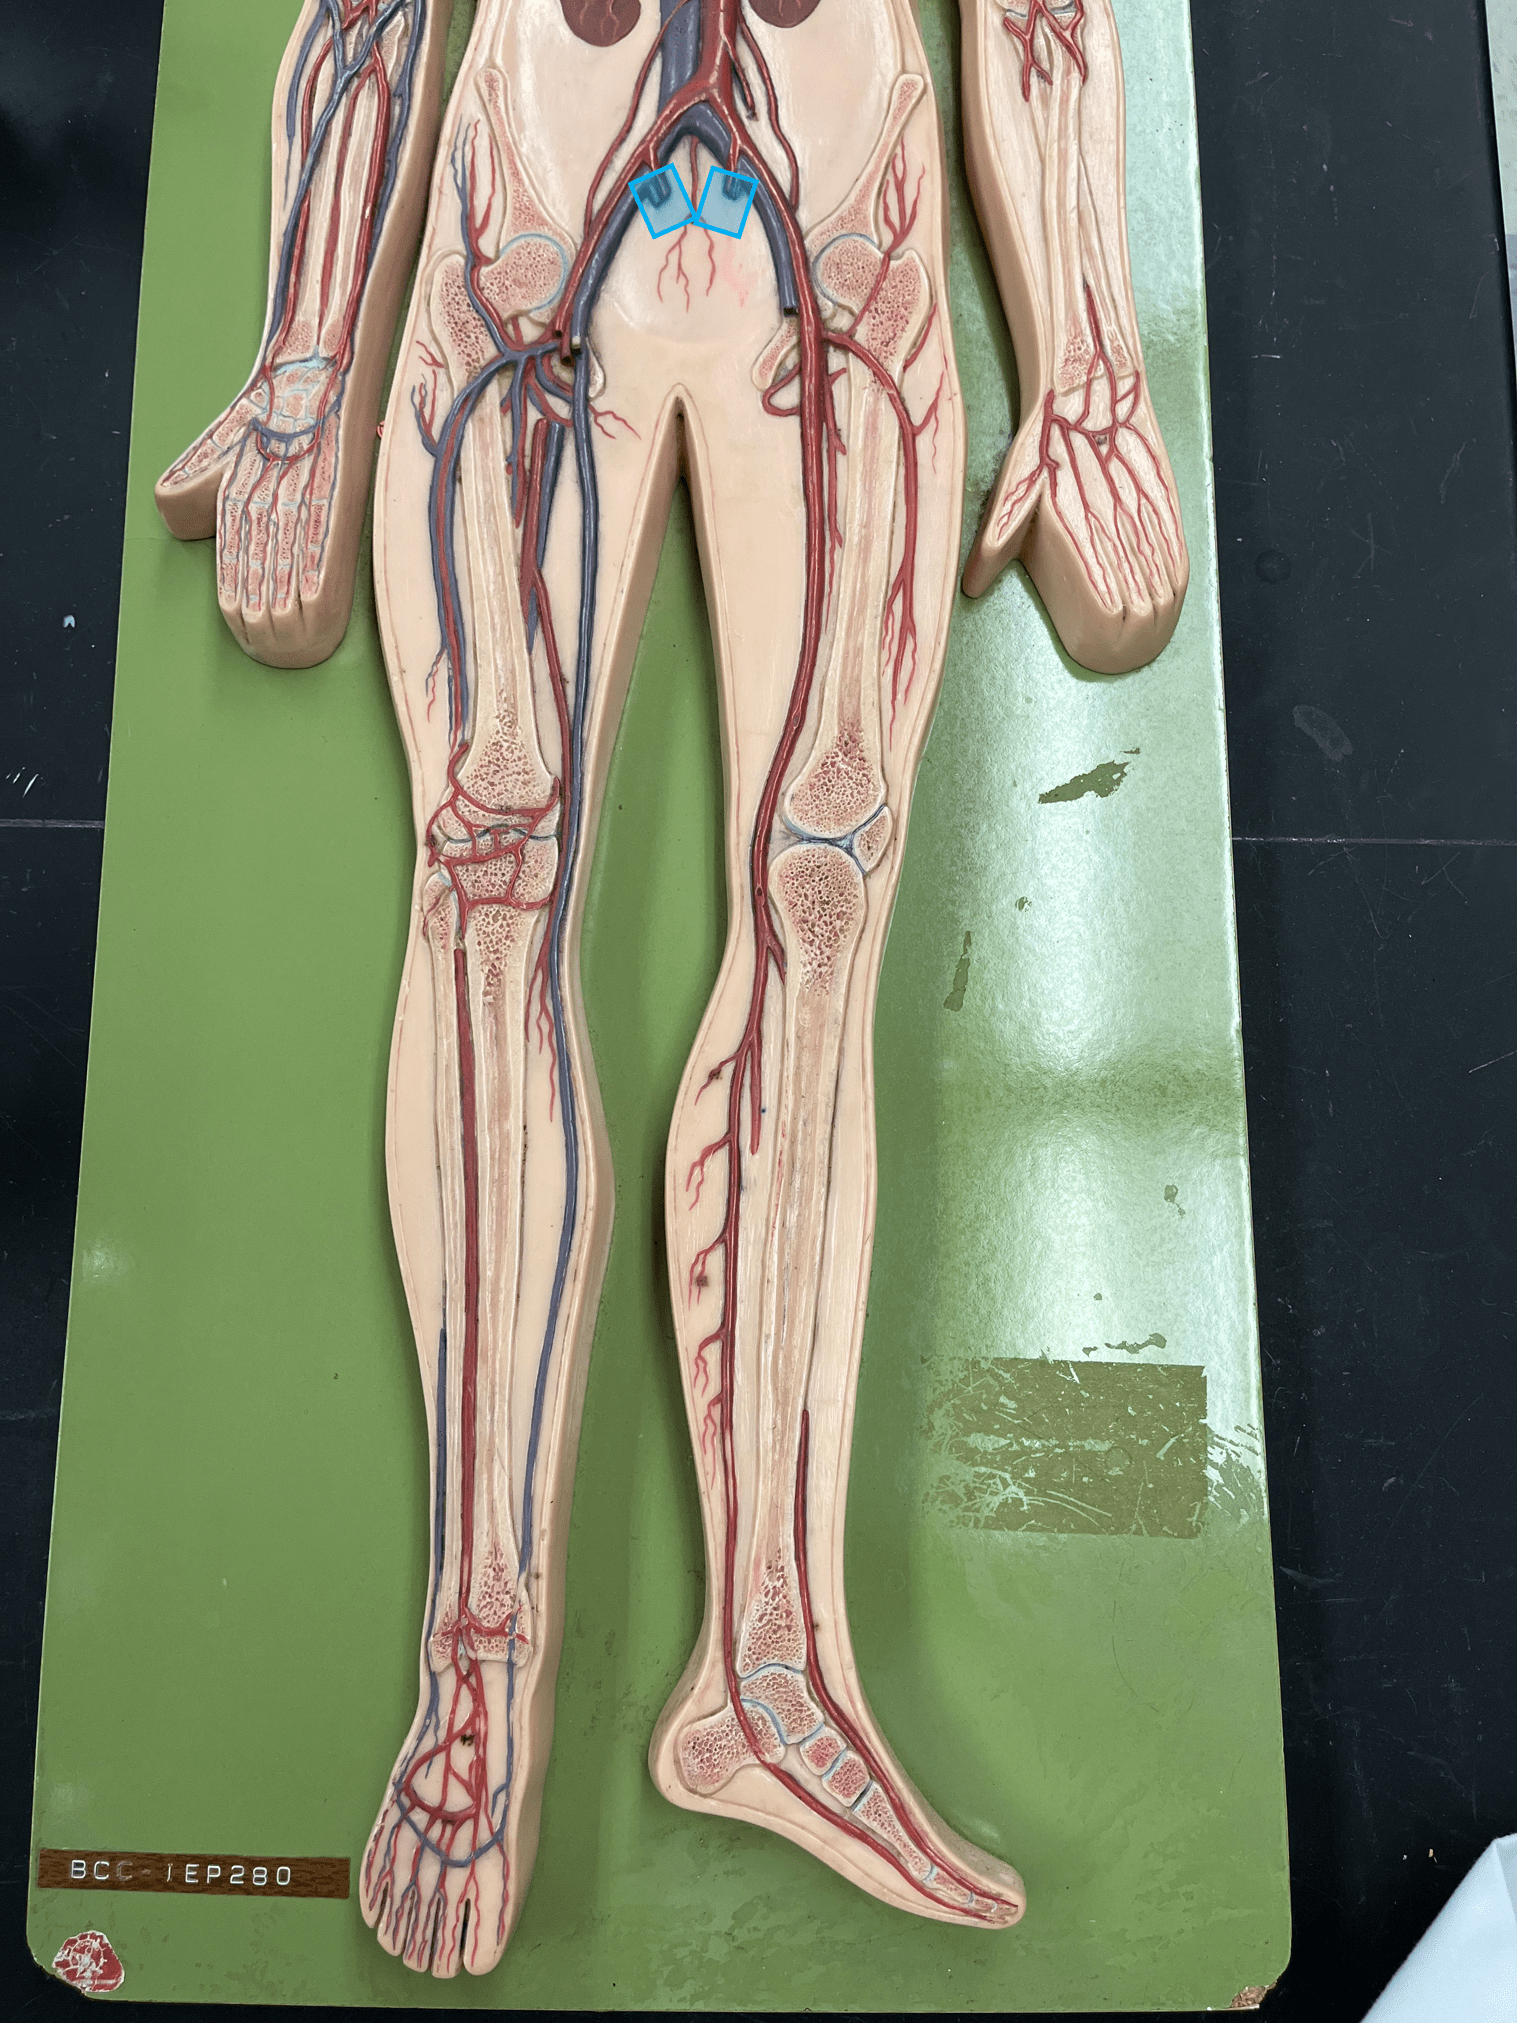

11

New cards

endothelium

• Part of the tunica interna.

• Originates from the brachiocephalic trunk (R.) or the aortic arch (L.).

• Supplies the head and neck through its branches.

• Originates from the brachiocephalic trunk (R.) or the aortic arch (L.).

• Supplies the head and neck through its branches.